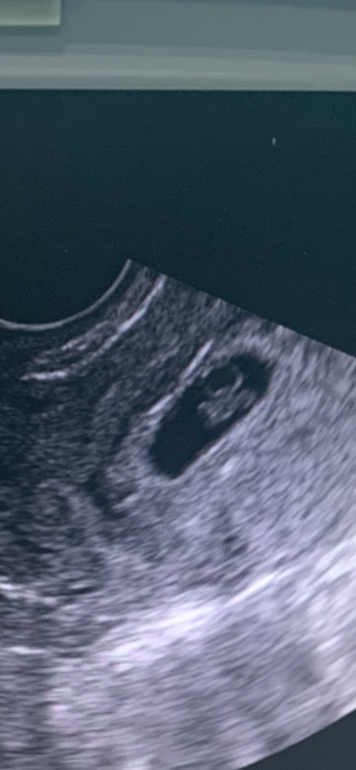

Если приблизить фото, то можно и второго эмбриона рассмотреть😊 тем более если это только 6 недель. Но конечно дальше будет видно)

1 конечно! 2 плода иначе выглядят. Все тоже самое что у вас только в двойном количестве.

Один, кто тут двоих увидел, видимо не умылись утром

Один эмбрион и один Желточный мешок